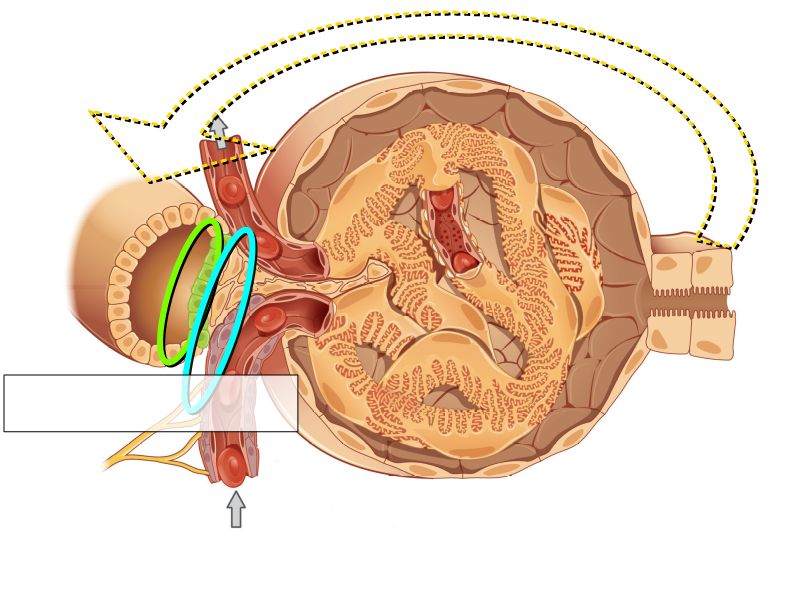

Kidney

- Capsule

- Cortex

- Medulla

- Multilobar

Multilobar

- Conical mass (pyramid)

- Medullary tissue

- capped with

- Cortex

- Delineated by

- Renal columns

- Apex of pyramid

- Papilla

- Projects into renal pelvis

Nephron

Nephron

- Renal corpuscle

- Proximal convoluted segment

- Long loop of Henle

- Descending portion

- Ascending portion

- Distal convoluted segment

Appearance

- Cortex

- Renal corpuscles

- Convoluted tubules

- Medulla

- Loops of Henle

- Collecting tubules

Kidney lobule

- Group of neprons

- Open into branches

- Same collecting duct

- Not clearly demarcated

- Interlobular arteries/veins